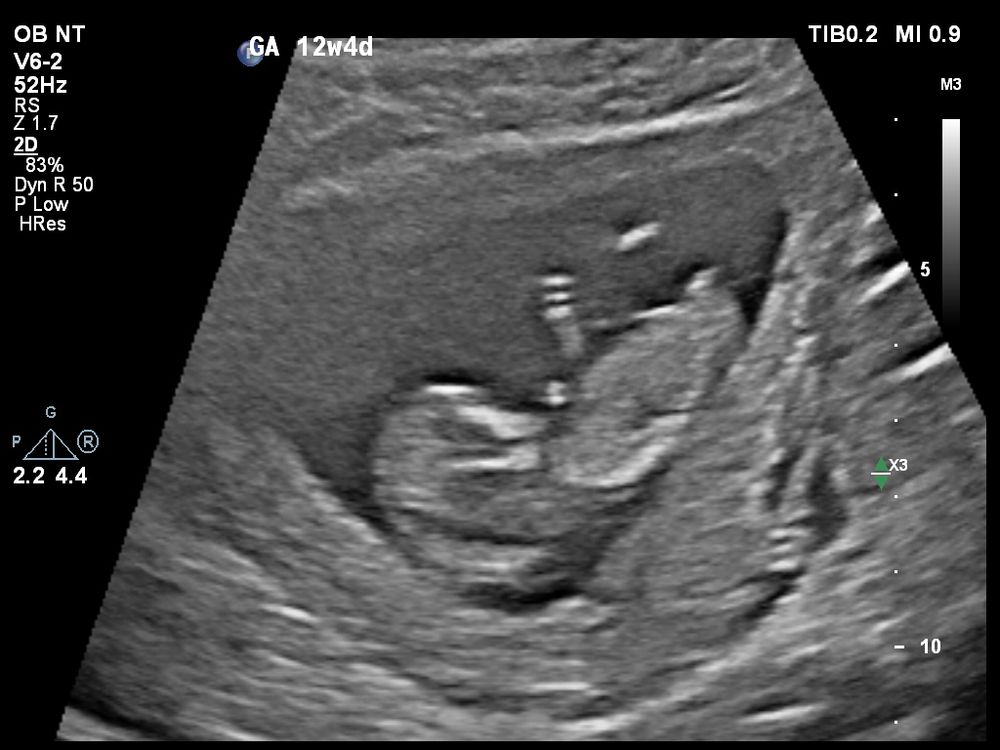

Сегодня сходили с молодым человеком на свидание с лялей 😊 Все у неё/него хорошо, показал(а) нам как плавает, ножки задирает (1 фото). Во время УЗИ мне показалось, что половой бугорок прямо смотрит, надеялась, что на видео/фотографиях все отмечено, а что-то как-то нет, наверное, не в настроении на фотографии был(а) 😀😅

По первым УЗИ (и по овуляции) сегодня срок 12+1, а по скринингу срок 12+5 (6.2см)😅